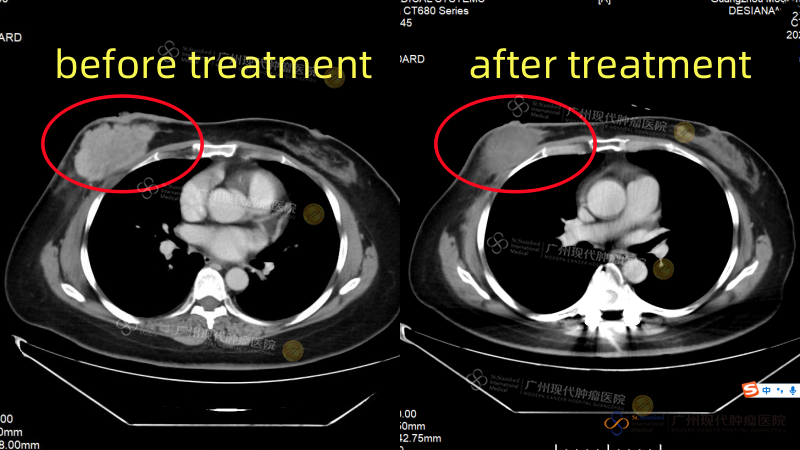

Seorang pasien kanker ginjal asal Indonesia, Tn. An (nama samaran), didiagnosis menderita karsinoma sel jernih ginjal di negaranya, namun tidak segera mendapatkan pengobatan yang efektif. Pada awal November 2024, saat datang ke rumah sakit, ia telah mengalami penyebaran kanker ke otak, paru-paru, dan beberapa bagian di tulang, serta kelumpuhan total. Setelah dilakukan diskusi dan evaluasi oleh tim MDT rumah sakit, dirumuskan rencana pengobatan individual berupa “terapi target dikombinasikan dengan imunoterapi”. Satu bulan kemudian, nyeri yang dialami Tn. An berkurang secara signifikan, dan kekuatan otot di kedua sisi tubuhnya mulai pulih secara bertahap. Evaluasi terakhir menunjukkan bahwa seluruh lesi metastasis dalam tubuhnya telah terkendali dengan baik. Kekuatan otot di kedua sisi pulih dari tingkat 1 menjadi tingkat 5, dan ia kini sudah dapat berdiri serta berjalan secara mandiri.

Paru-paru: Saat pertama kali dirawat di rumah sakit VS setelah pengobatan

Kedua tulang ilium: pada saat rawat inap kedua VS setelah pengobatan